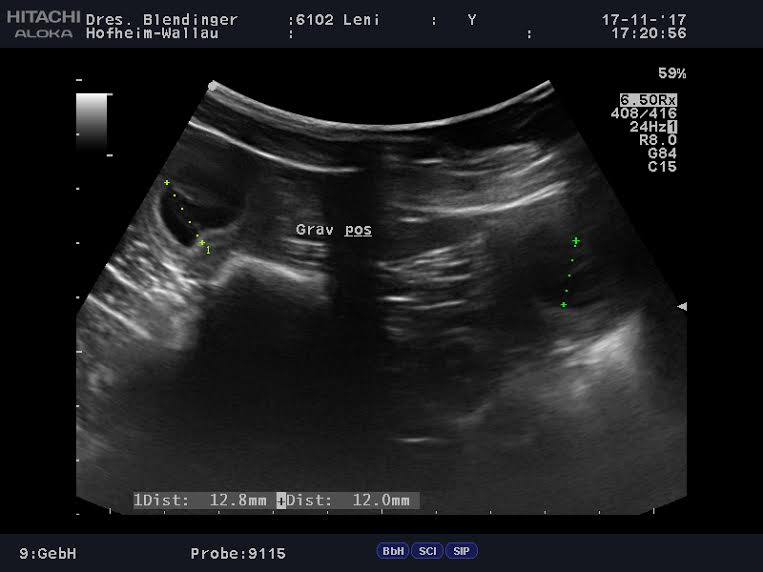

Juchhu!!! Leni ist tragend... wir hoffen auf eine gut verlaufende Trächtigkeit...

... und freuen uns auf kleine Weihnachtswichtelwelpen :O)